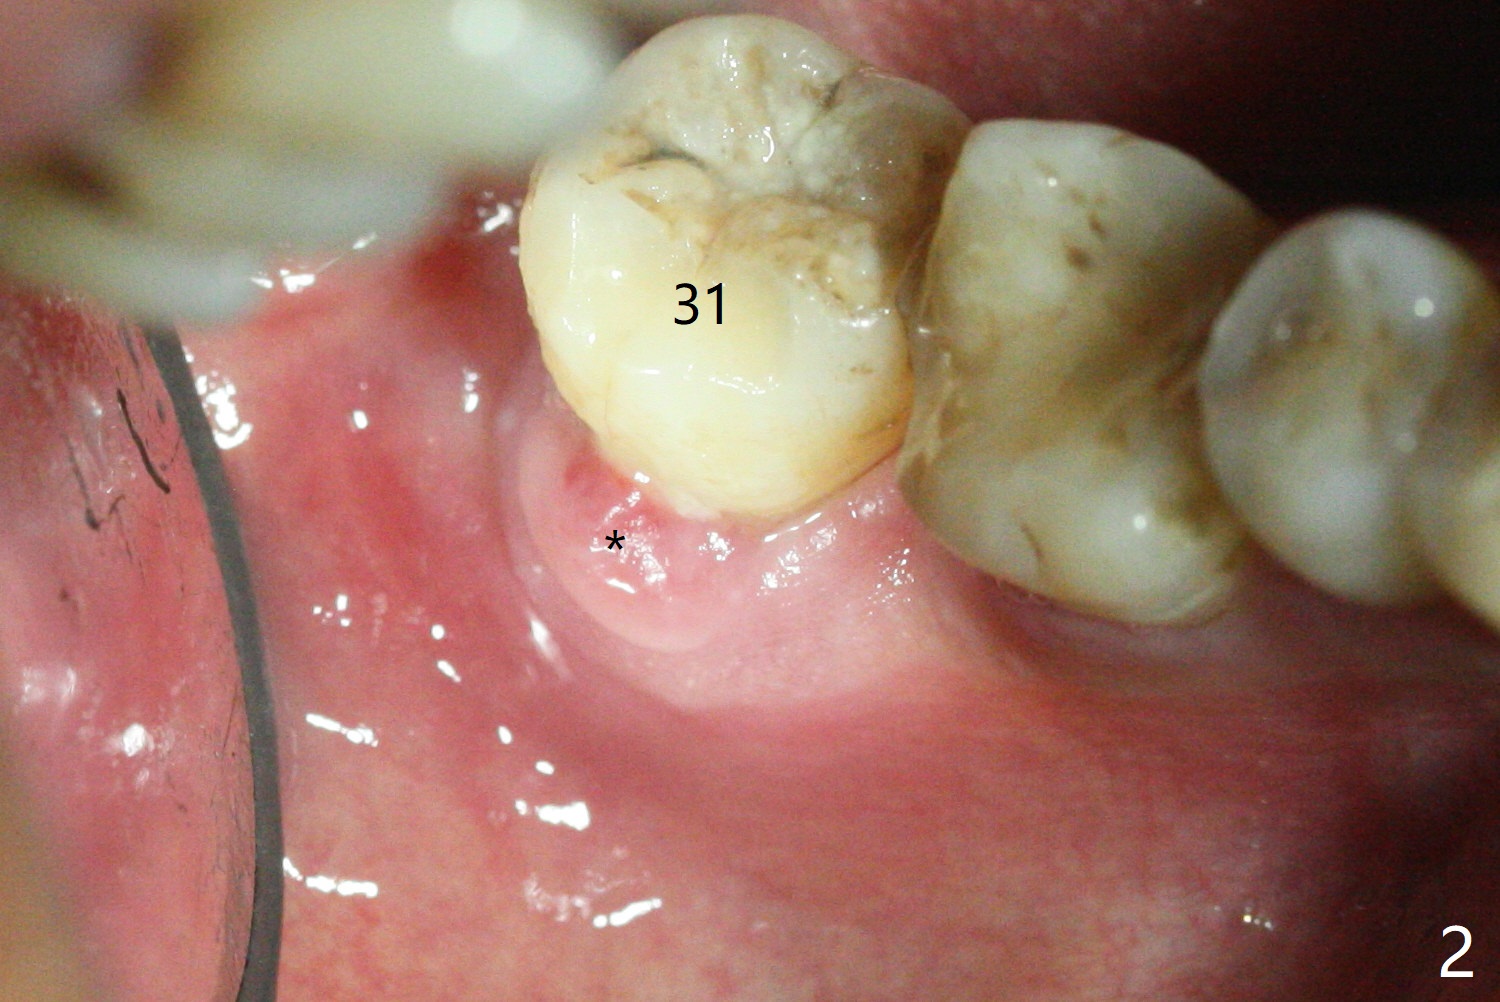

After removing the fractured apices of the tooth #31 (Fig.1,2), it is extremely difficult to start osteotomy with 7.3 mm stopper free hand. Since sticky bone (Fig.3,4) and PRF membrane are available, socket preservation is performed with bone condenser and PGA (Fig.5). If a surgical guide were fabricated, immediate implant would finish quicker. The socket opening is almost closed without pain or swelling 8 days postop (Fig.6). Clinically, the ridge is apparently wide with enough keratinized gingiva 4.5 months postop. The original ridge height seems to restore as the sticky bone undergoes condensation vertically (Fig.7, as compared to Fig.5). With bone graft, a 1.5 mm longer implant could be placed (Fig.8). The gingival pocket (Fig.9 white dashed line) seems to be an excellent cultivation bed for bone graft, although the latter also undergoes buccolingual shrinkage coronally (Fig.10).